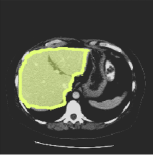

Consider a three-dimensional object within a volume. It is straightforward to produce a 3D bounding box of the object by finding its extreme points in the three coordinate axes. While this 3D bounding box will be tight in the 3D sense, its rectangular cross-sections will not, in general, remain tight with respect to the planar cross-sections of the volume. Fig. 1 illustrates such a case for the task of liver segmentation in a CT volume. In the Experiments section we show that the success of existing 2D weakly-supervised segmentation methods relies on the bounding boxes being tight and therefore the tightness of the individual 2D bounding boxes should be corrected before training and applying a segmentation CNN.

(a)

(b)

(c)

(d)

The global bounding box tightness prior mentioned above assumes that each of side of the box is sufficiently close to the target region. This means that for any region shape, each vertical or horizontal line inside the bounding box will cross at least one pixel belonging to the target region. This condition does not hold when the provided annotation comes as a 3D bounding box which is represented as a series of per-slice non-tight 2D bounding boxes. In this case, there will exist vertical or horizontal lines shown as stripes in Fig. 1 (d), that will lie outside of the actual object boundary. In the Experiments section we demonstrate the poor performance of the weakly-supervised approach from [5] when the user-provided bounding box is much wider than the true object of interest.